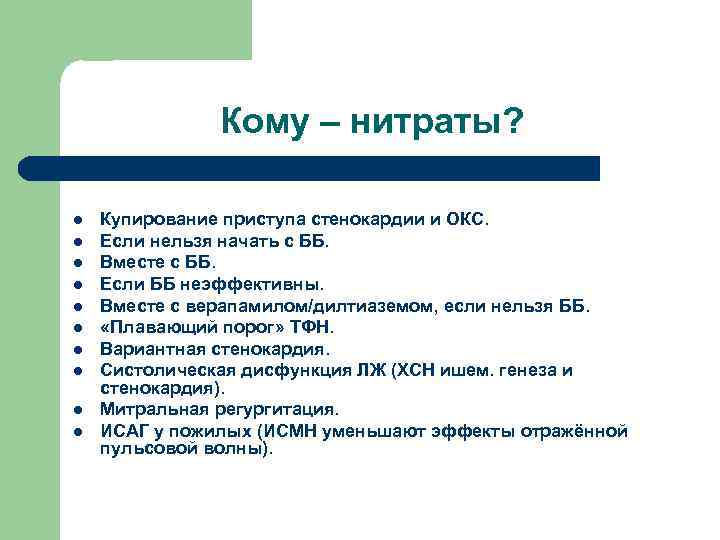

Кому – нитраты? l l l l l Купирование приступа стенокардии и ОКС. Если нельзя начать с ББ. Вместе с ББ. Если ББ неэффективны. Вместе с верапамилом/дилтиаземом, если нельзя ББ. «Плавающий порог» ТФН. Вариантная стенокардия. Систолическая дисфункция ЛЖ (ХСН ишем. генеза и стенокардия). Митральная регургитация. ИСАГ у пожилых (ИСМН уменьшают эффекты отражённой пульсовой волны).